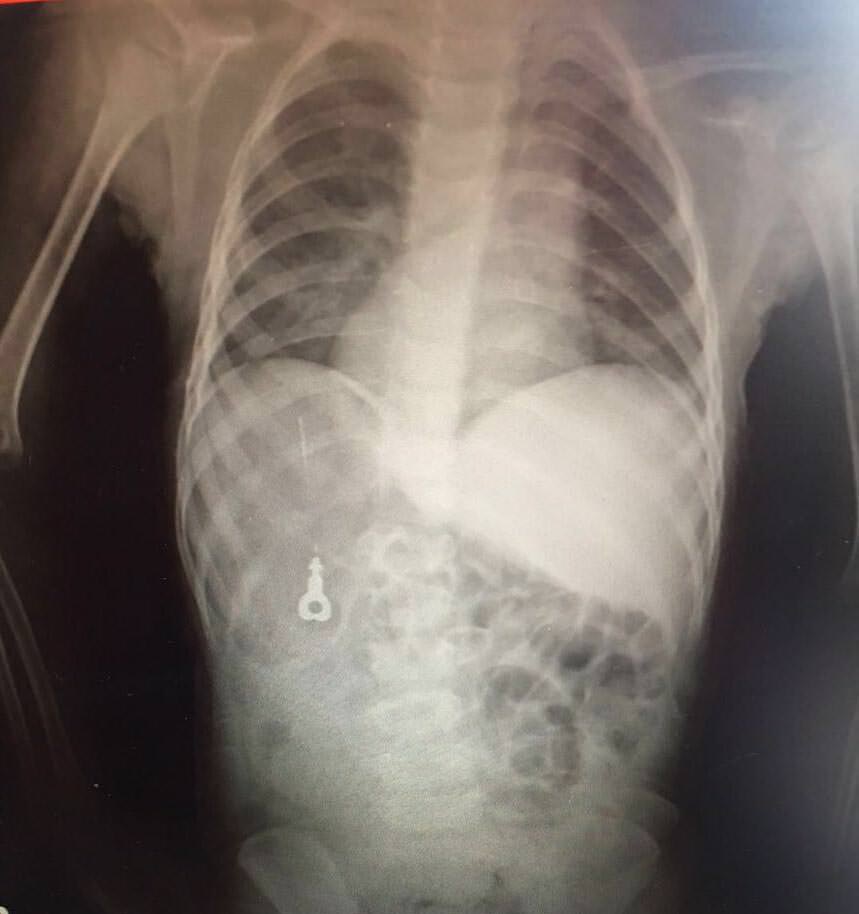

Bu objelerden en tehlikelisinin piller olduğuna dikkat çeken Doç.Dr. Maşallah Baran, "Piller kimyasal mekanizmayla mukozayı yakıyor, özellikle yemek borusu çok duyarlı pillere, hele ki yeni takılmış bir pilse saatler içinde şahit olduğum bir kaç vaka var, yemek borusunu kömür haline getirebiliyor" dedi.

Tepecik Eğitim ve Araştırma Hastanesi Çocuk Gastroenteroloji Bölümü'nde görevli Doç.Dr. Maşallah Baran, Dr. Miray Karakoyun, Dr. Yeliz Appak, hemşire Sevda Yalçınkaya ve hemşire Makbule Savurgan, çocukların yuttuğu yabancı cisimleri operasyonla çıkartıyor. "